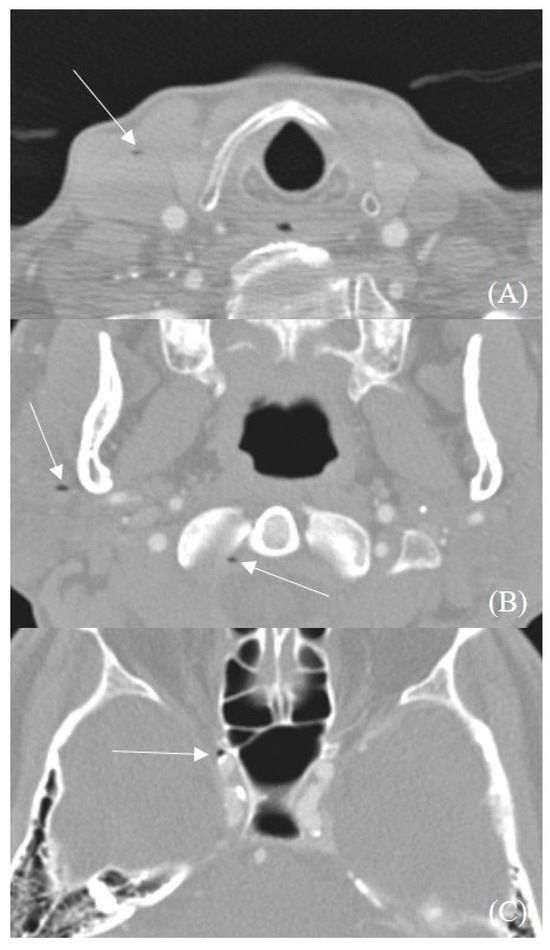

2. Materials and Methods

2.1. Patient Selection

2.2. Imaging Protocol

2.3. Image Interpretation